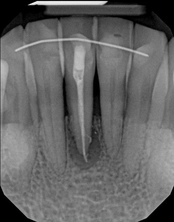

Apicoectomy:

Before, the failed root canal

Immediately after the microsuregery

3-months after shows complete healingThe patient was told by a specialist that the root canal failed, the only option was extraction and an implant. She did not want to do that; she wanted to keep her tooth, after all, it is her front tooth. She found us. We performed an apical microsurgery with the laser. The tooth was saved and is still functioning. This is a poor area for an implant, so much better to save the tooth.